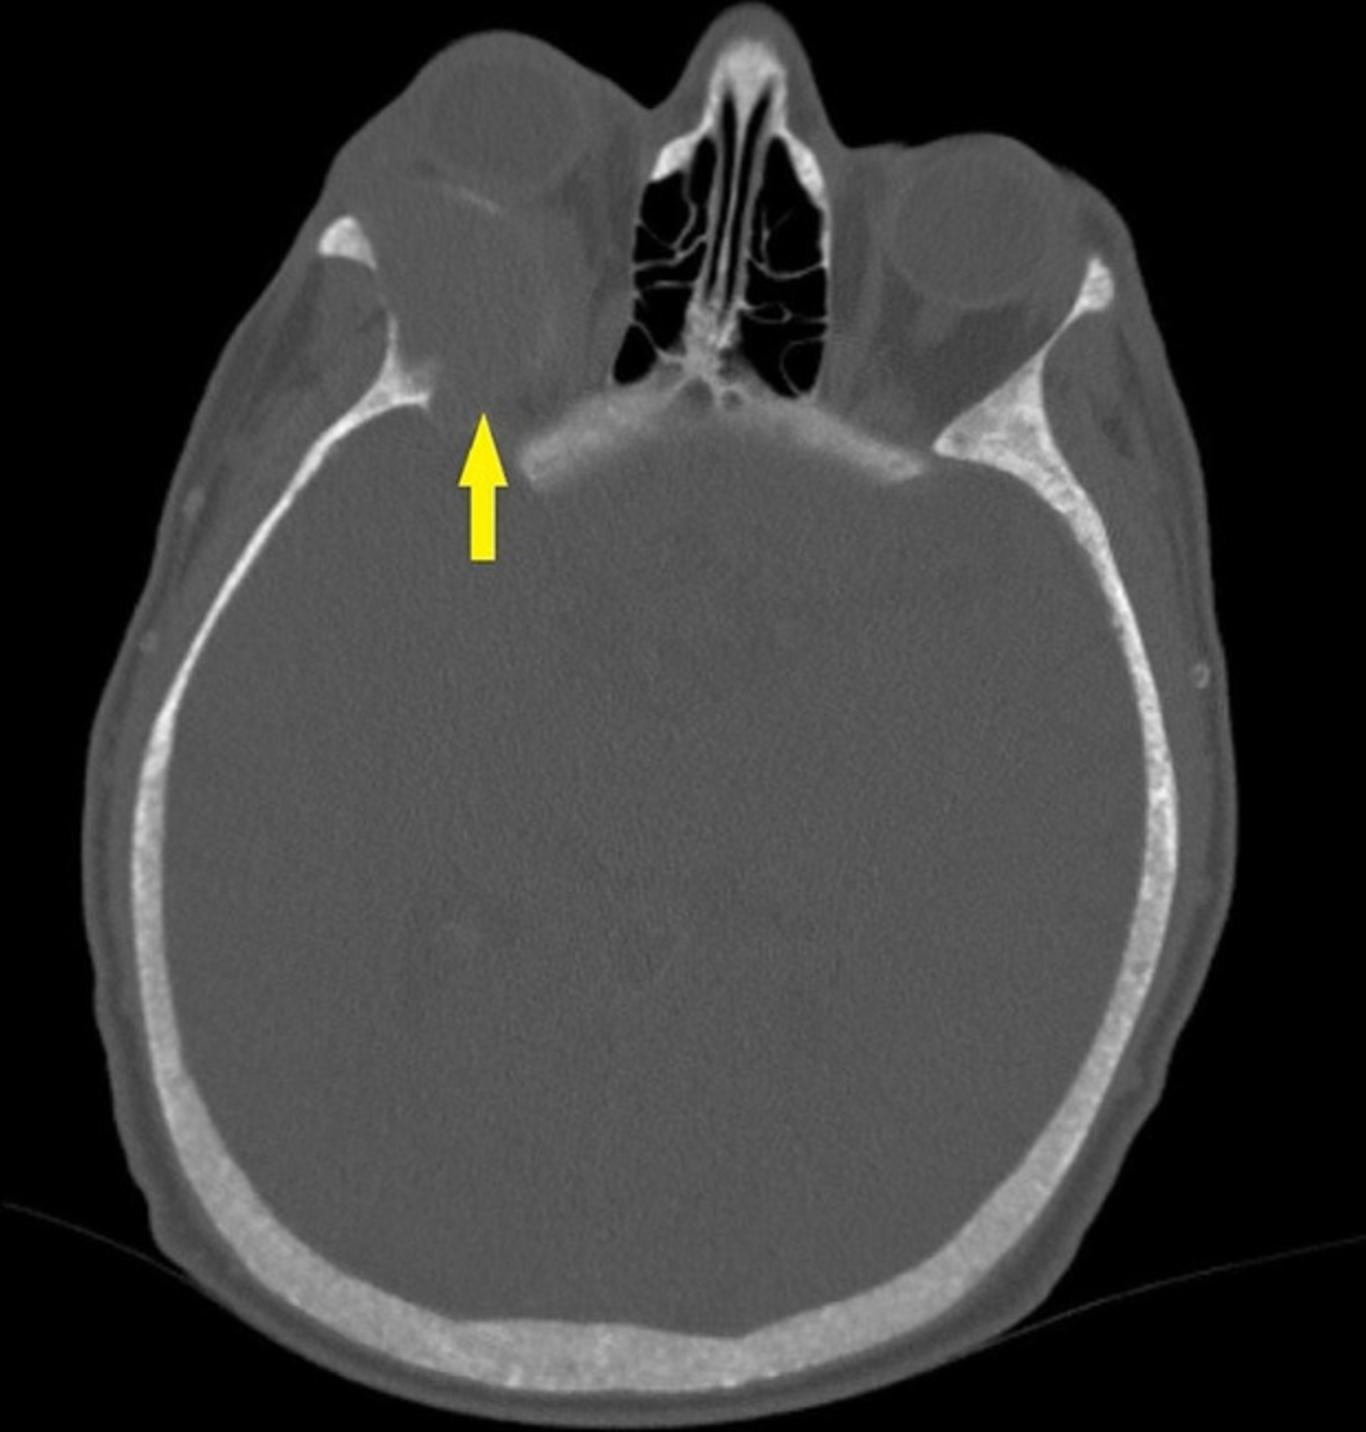

磁共振成像(MRI)眼眶和颅骨检查发现在右眼眶后外侧一个眶外肿块。肿块压迫额骨眶部、右侧视神经和上直肌。病变尺寸为36*27*24mm,MRI表现出弥散均匀对比增强。肿瘤病变在T1加权图像上表现为轻微高信号,在T2加权图像上显示为低信号。MRI如图1所示。CT扫描显示,右侧眼眶后外侧有一个膨胀性肿块,伴有外周线性钙化,起源于蝶骨翼(图2)。肿块病变导致相邻骨结构侵蚀,被归类为BT。

图2 颅骨CT图像。箭头显示肿瘤病变伴周围线性钙化